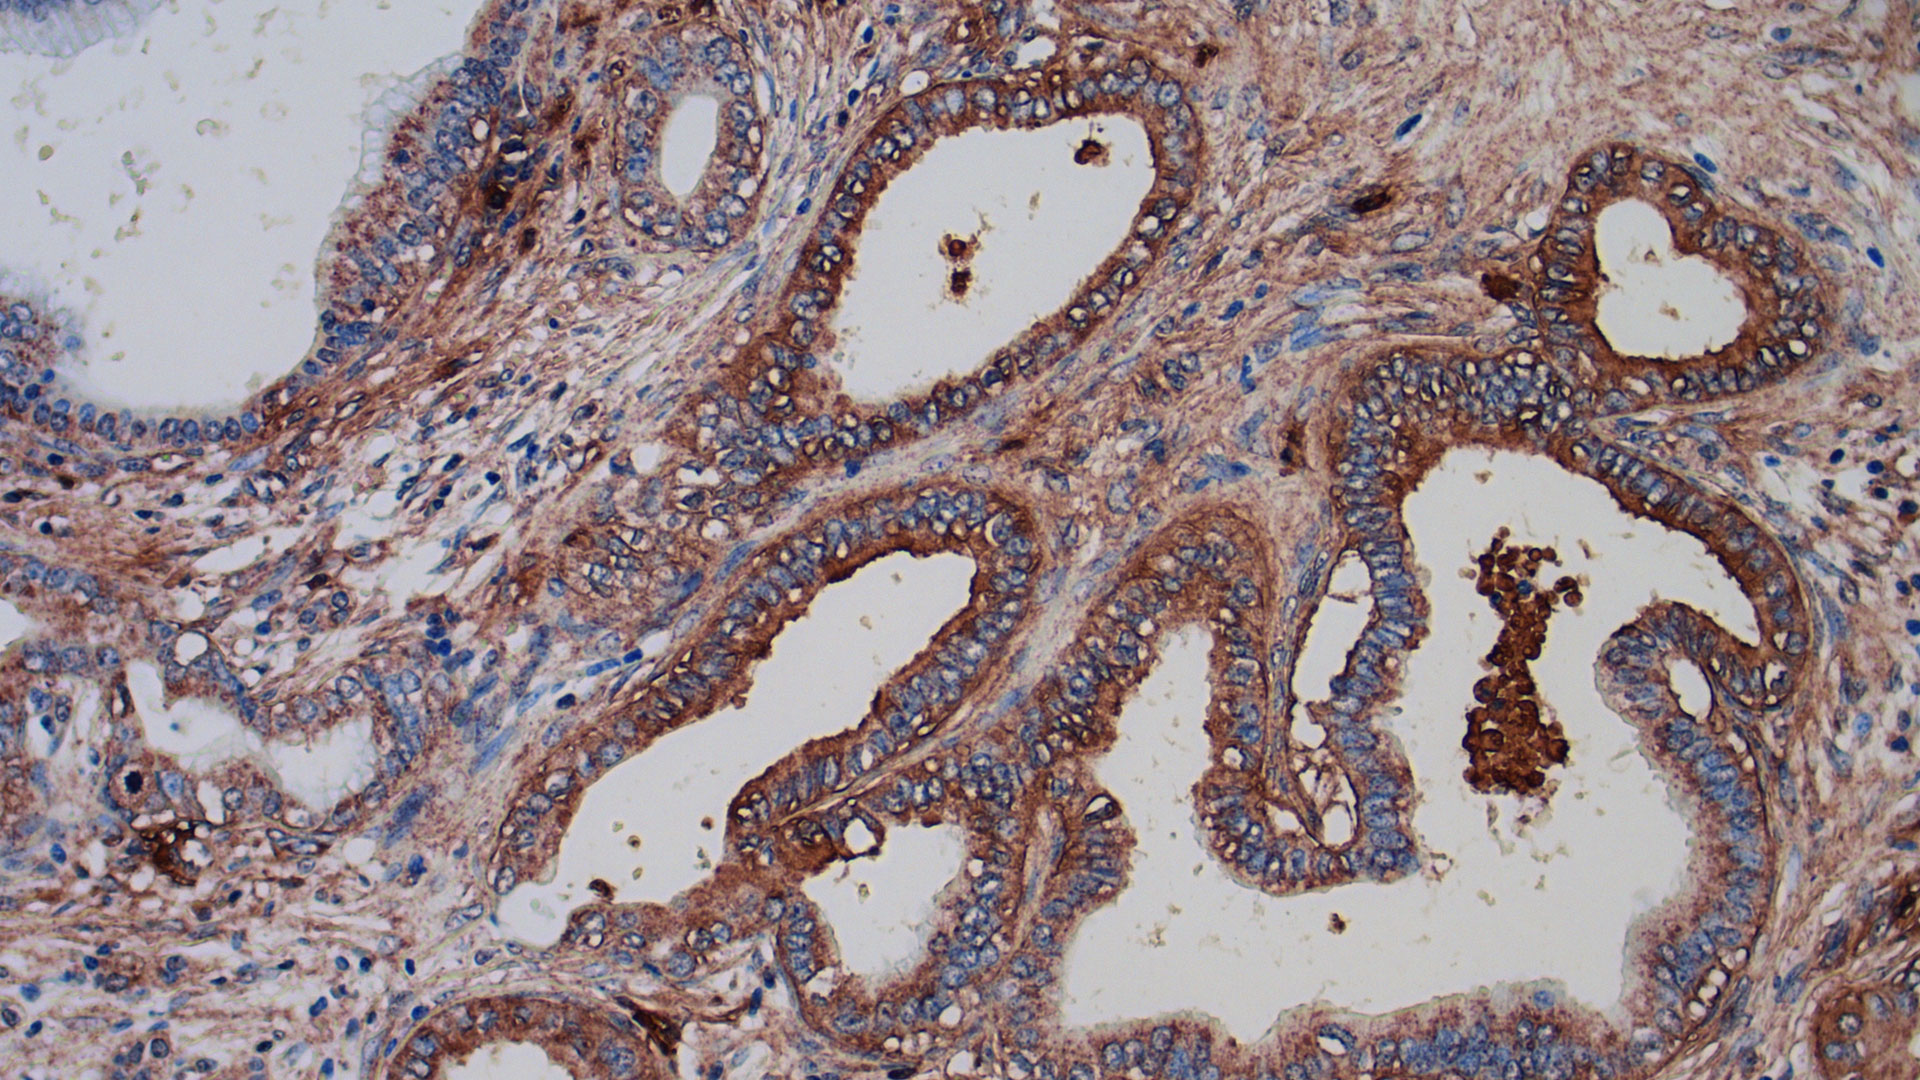

SRIの研究者、膵臓がんを標的として治療するバイオマーカーを特定

膵臓がんを標的とする分子を、SRIのFOX Three分子誘導システムを活用して開発

SRIの科学者がグライコミクスのプロトコルを科学界に公開

微生物やがんの糖鎖シグネチャーを探索する戦略を語る